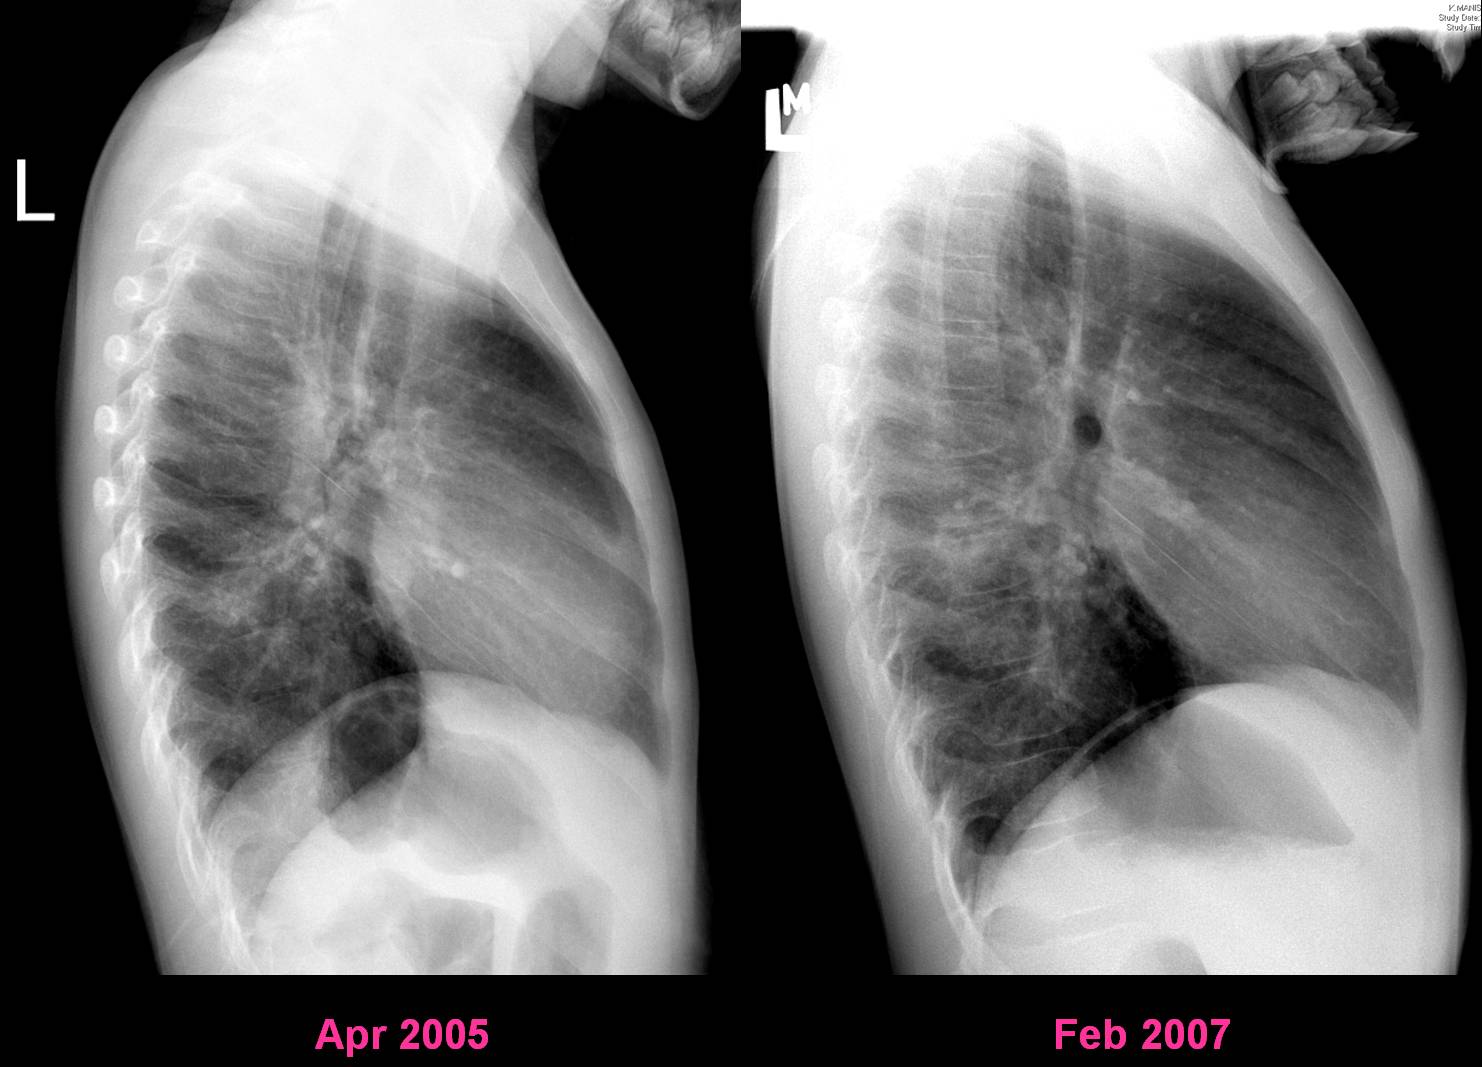

| Figure 3-a | Figure 3-b |